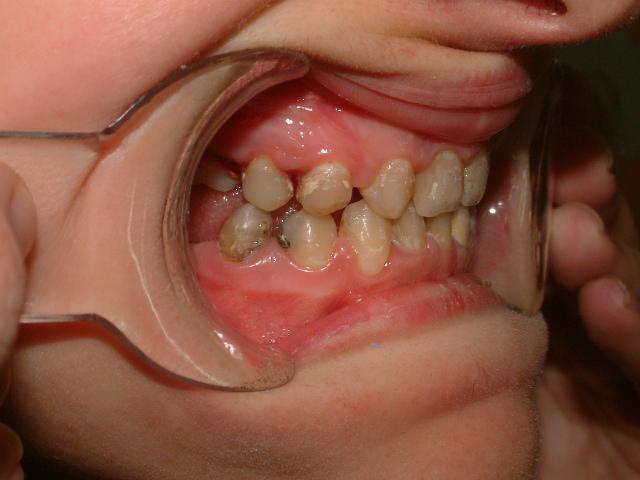

Στην συγκεκριμένη περίπτωση η παρουσία οδοντωμάτων εμποδίζει την ανατολή των μόνιμων κεντρικών τομέων καθιστώντας τα έγκλειστα.

H έγκαιρη παρέμβαση λύνει το πρόβλημα με την χειρουργική απομάκρυνση των οδοντομάτων και με την υποβοηθούμενη μετατόπιση των κυρίως δοντιών με ορθοδοντικές δυνάμεις.